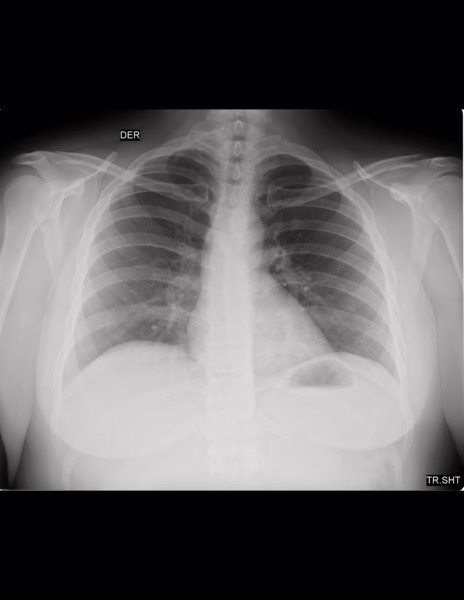

LA PROYECCION RADIOLOGICA OBTENIDA NOS MUESTRA LOS SIGUIENTES HALLAZGOS:

-Tejidos blandos son simétricos, con adecuada densidad y grosor.

-Estructuras óseas, sin evidencia de lesiones líticas, blásticas o perdida de la contigüidad.

-Vía aérea permeable, central. Botón aórtico sin calcificaciones.

-Mediastino, conservando sus diámetros.

-Corazón, central, con índice cardiotorácico menor de 0.5

-Hilios pulmonares, sin alteraciones.

-Trama bronco-vascular, con adecuado trayecto, con adecuada densidad.

-Campos pulmonares, hacia parénquima pulmonar derecho, a nivel basal con presencia de imagen ovoidea, homogéneas, radiopacas, regular, bien definida, que mide 4.2 X 3.7 mm. Parénquima pulmonar izquierdo, hacia área para hiliar en segmentos inferiores, con presencia de imágenes, ovoidea, homogéneas, radiopacas, regulares, bien definidas, que miden 3.3 X5 mm, 2.9 X 5.2 mm, 5.6 X 3.4 mm.

-Recesos costofrénicos y cardiofrénicos se observan libres.

OPINIÓN RADIOLÓGICA:

EN EL PRESENTE ESTUDIO RADIOGRÁFICO, SIN EVIDENCIA DE LESIONES PARENQUIMATOSAS.

HACIA NIVEL BASAL DE PULMÓN DERECHO Y PARA HILIAR INFERIOR DE PULMÓN IZQUIERDO CON IMÁGENES SUGERENTES DE MICRONÓDULOS VS GANGLIOS DE CARACTERÍSTICAS BENIGNAS.

LEER DESCRIPCIÓN Y OTORGAR VALOR DIAGNÓSTICO.

CORRELACIONAR CON DATOS E HISTORIA CLINICA DEL PACIENTE